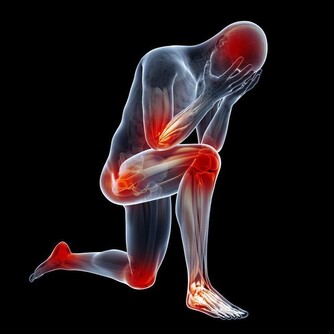

8. 強直性脊柱炎

強直性脊柱炎是一種影響脊柱的關節炎,會引起脊柱骨骼和脊柱與骨盆之間關節的炎症。症狀包括下背部和臀部疼痛與僵硬,它帶來的疼痛可能非常嚴重,以至於讓人徹夜不眠。